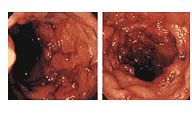

병변

• 대장 내시경으로 들여다보면 장벽의 점막이 빨갛게 붓고, 출혈하기 쉬운 상태를 보입니다. 또 여기저기에 염증이나 궤양이 보입니다. 궤양의 주위가 버섯모양으로 불룩 올라오거나(위용종), 요철이 생기기도 합니다.